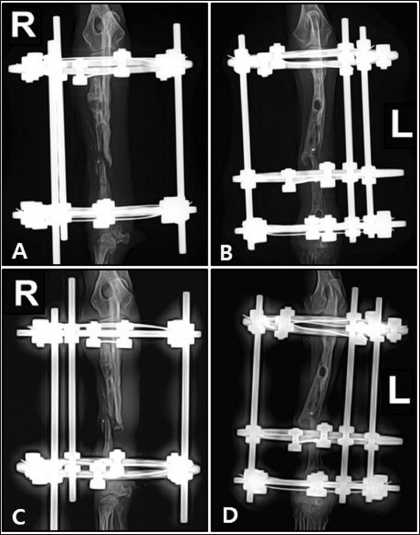

Preoperative medications for both surgeries included tramadol (5 mg/kg, IV), cefazolin (30 mg/kg, IV), famotidine (0.5 mg/kg, IV), and midazolam (0.2 mg/kg, IV). General anesthesia was induced with propofol (5 mg/kg, IV) and maintained with 1.5%–2% isoflurane in oxygen. Intraoperative analgesia was provided by a constant-rate infusion of ketamine and lidocaine. The forelimbs were then prepared for routine aseptic surgery. The entire surgery lasted 2 hours and 50 minutes. Postoperatively, cefazolin was administered for 5 days, along with tramadol and meloxicam (0.1 mg/kg, SC) for pain management. Amoxicillin syrup was prescribed for an additional 3 weeks as an antibiotic. Sutures were removed in the second postoperative week, and ongoing physical rehabilitation was implemented. External fixation devices were removed in the fourth postoperative week. Radiographic assessments showed a union of the right radius by the eighth postoperative week and the left radius by the tenth postoperative week (Fig. 4). Although forelimb ambulation remained plantigrade, the dog’s overall gait improved, enabling consistent quadrupedal movement.

Fig. 4. Lateral radiograph 10 weeks after the second surgery showing bone union progression.

Previous studies have highlighted challenges in using external fixation in toy-breed dogs due to their size, particularly in the radius (Hamilton and Langleyhobbs, 2005). However, based on the author’s clinical experience with successful CEF applications, this study initially applied CEF for temporary fixation to promote the reconstruction of lysed bone and stabilize surrounding soft tissue. Rehabilitation was performed to maintain joint function, promote vascularization, and enhance muscle mass until a second surgery was conducted. Although radiographic evaluation revealed no signs of union at the fracture site, the frequency of forelimb use increased after temporary fixation. Six weeks after the first surgery, radiography showed increased bone thickness and a decrease in the areas of lysis. In the second surgery, the fracture was reduced using plates and screws, and CEF was applied simultaneously for 4 weeks. During the 10 weeks of CEF application, no complications such as infections or implant loosening were observed, and it provided the necessary stability to maintain alignment and regenerate the bone.